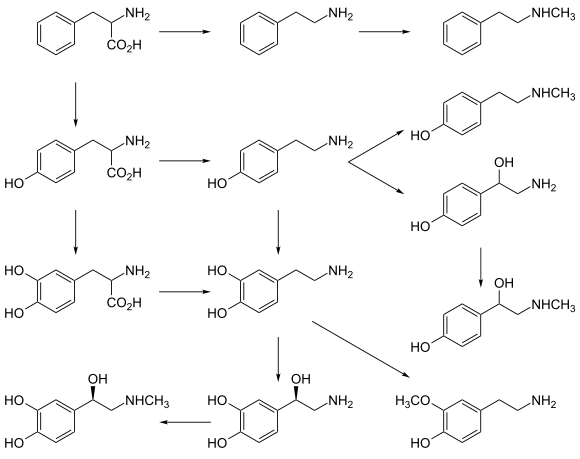

Dopamine beta-hydroxylase catalyzes the hydroxylation of not only dopamine but also other phenylethylamine derivatives when available. The minimum requirement seems to be the phenylethylamine skeleton: a benzene ring with a two-carbon side chain that terminates in an amino group.[6]

DBH primarily contributes to catecholamine and trace amine biosynthesis. It also participates in the metabolism of xenobiotics related to these substances; for example, the human DBH enzyme catalyzes the beta-hydroxylation of amphetamine and para-hydroxyamphetamine, producing norephedrine and para-hydroxynorephedrine respectively.[21][22][23]

The systematic name of this enzyme class is 3,4-dihydroxyphenethylamine, ascorbate:oxygen oxidoreductase (beta-hydroxylating).